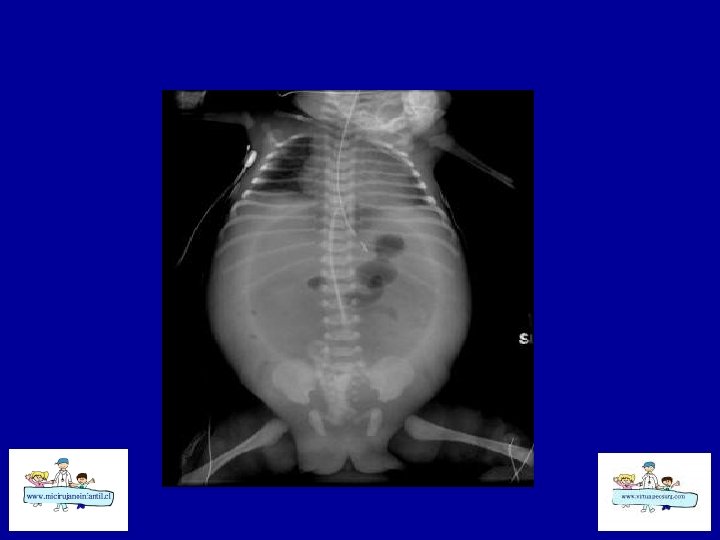

ECN-RADIOLOGÍA SIMPLE • • Distensión de asas Pneumatosis intestinal Asa fija (centinela) Gas Porta Edema de pared Ascitis Aire libre

ECN- CLASIFICACION (Bell) Etapa I: sospecha a CEG, sepsis inicial, Rx. distensión de asas moderada Etapa II: confirmada Ileo, sepsis más intensa , Rx: Ileo – pneumatosis b Hematoquezia Celulitis de pared, masa, grave, Rx: ascitis, gas porta Etapa III: grave Muy grave, CID, peritonitis Rx: ascitis Rx : pneumope ritoneo